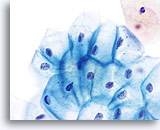

Postpartum

HSIL in a postpartum sample. Note the increased N/C ratio and abnormal chromatin in the HSIL cells as compared to the parabasal cells, apparent even at low magnification.

20X